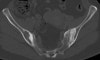

CT : 장골치밀화골염(Osteitis condensans ilii)

천장관절의 장골면에 삼각형(triangular)의 골경화가 주로 양측성으로 발생하며 간혹 일측성인 경우도 있습니다.